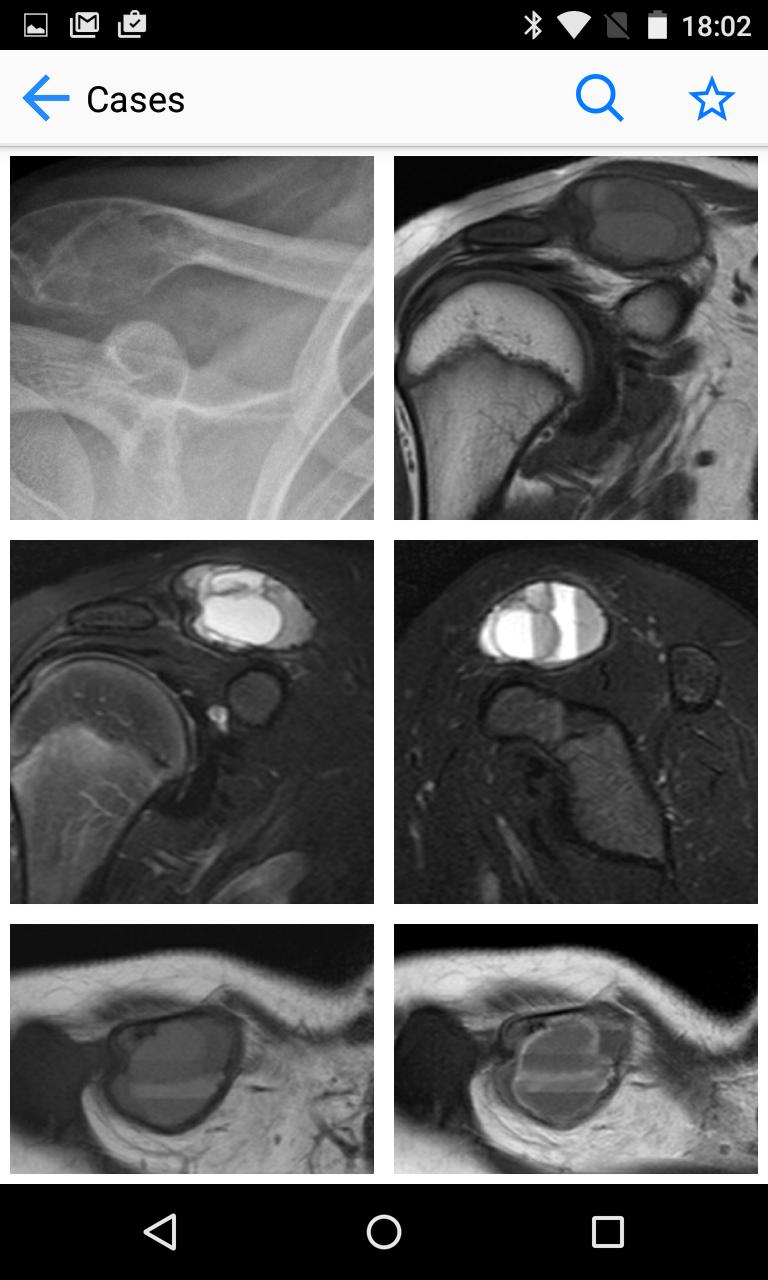

Estudios de caso de tumores de huesos y tejidos blandos. Una fuente de casos tumorales MSK/sarcoma.

BoSTT trae al usuario una experiencia real de casos frecuentes y raros, típicos y más inusuales de tumores de huesos y tejidos blandos. Cada caso tiene antecedentes clínicos, imágenes de radiología y patología de alta resolución, diagnóstico, tratamiento y puntos de aprendizaje.

La aplicación está diseñada para un profesional de la salud que trabaja en el campo de la atención médica musculoesquelética, incluidos radiólogos, patólogos, cirujanos ortopédicos, oncólogos, enfermeras especialistas y fisioterapeutas. También puede ser utilizado por estudiantes de medicina, aprendices, residentes y becarios especializados para la educación médica continua.